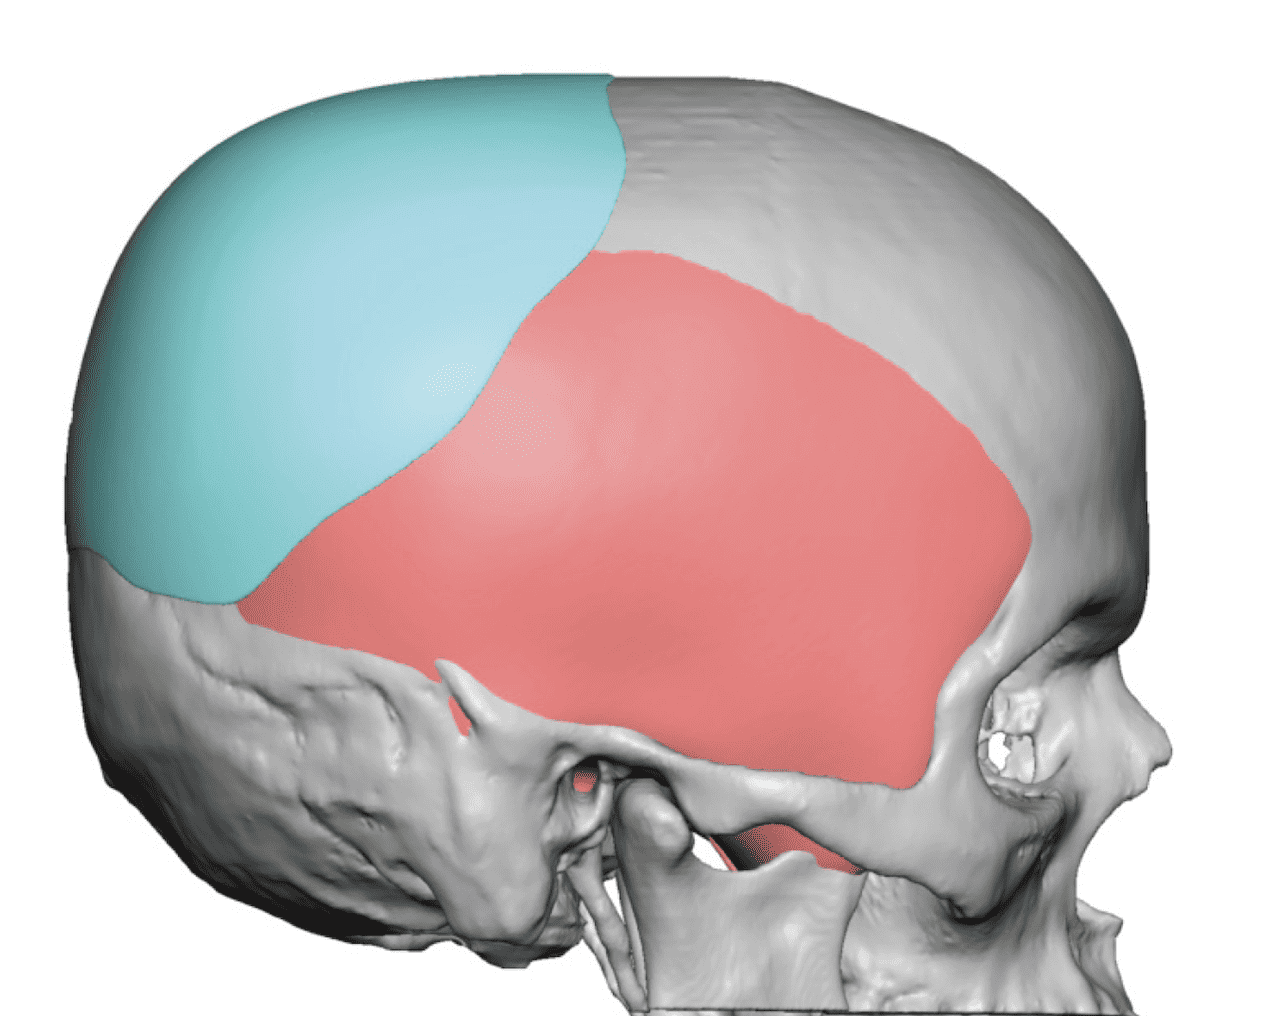

Desire for rounder shape to the top of the head from a congenital parasagittal deficiency skull shape.

Custom skull implant designed to fill in the parasagittal deficiencies.

Desire for rounder shape to the top of the head from a congenital parasagittal deficiency skull shape.

Custom skull implant designed to fill in the parasagittal deficiencies.